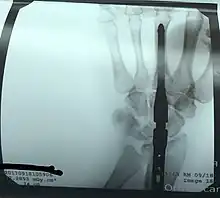

Radiographie après l’arthrodèse du poignet.